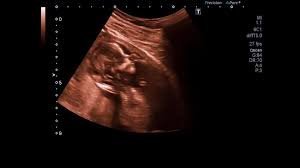

Their story is not unique. According to the latest government Population Statement, Australia’s total fertility rate (TFR) is expected to drop to 1.42 children per woman in 2025-26, well below the replacement level of 2.1. This decline is being driven by parents postponing parenthood, having fewer children, or choosing not to have children at all, with financial pressure, childcare costs, and career demands all playing a role.

Their experience is reflective of a broader shift in when Australians are having children and how many. According to the Centre for Population, many people are now having their first child in their early thirties rather than their mid-twenties. Fertility specialist Charley Zheng notes that IVF cannot fully overcome the biological clock, and the quality and quantity of eggs decline significantly with age.